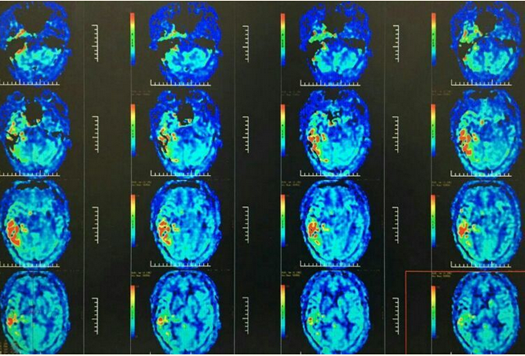

患者男,54岁,2016-4-14因“发作性右侧肢体无力12天”入院。MR灌注提示:双侧额顶叶及左侧颞枕叶大片状低灌注区。予以药物治疗两周症状明显好转出院。